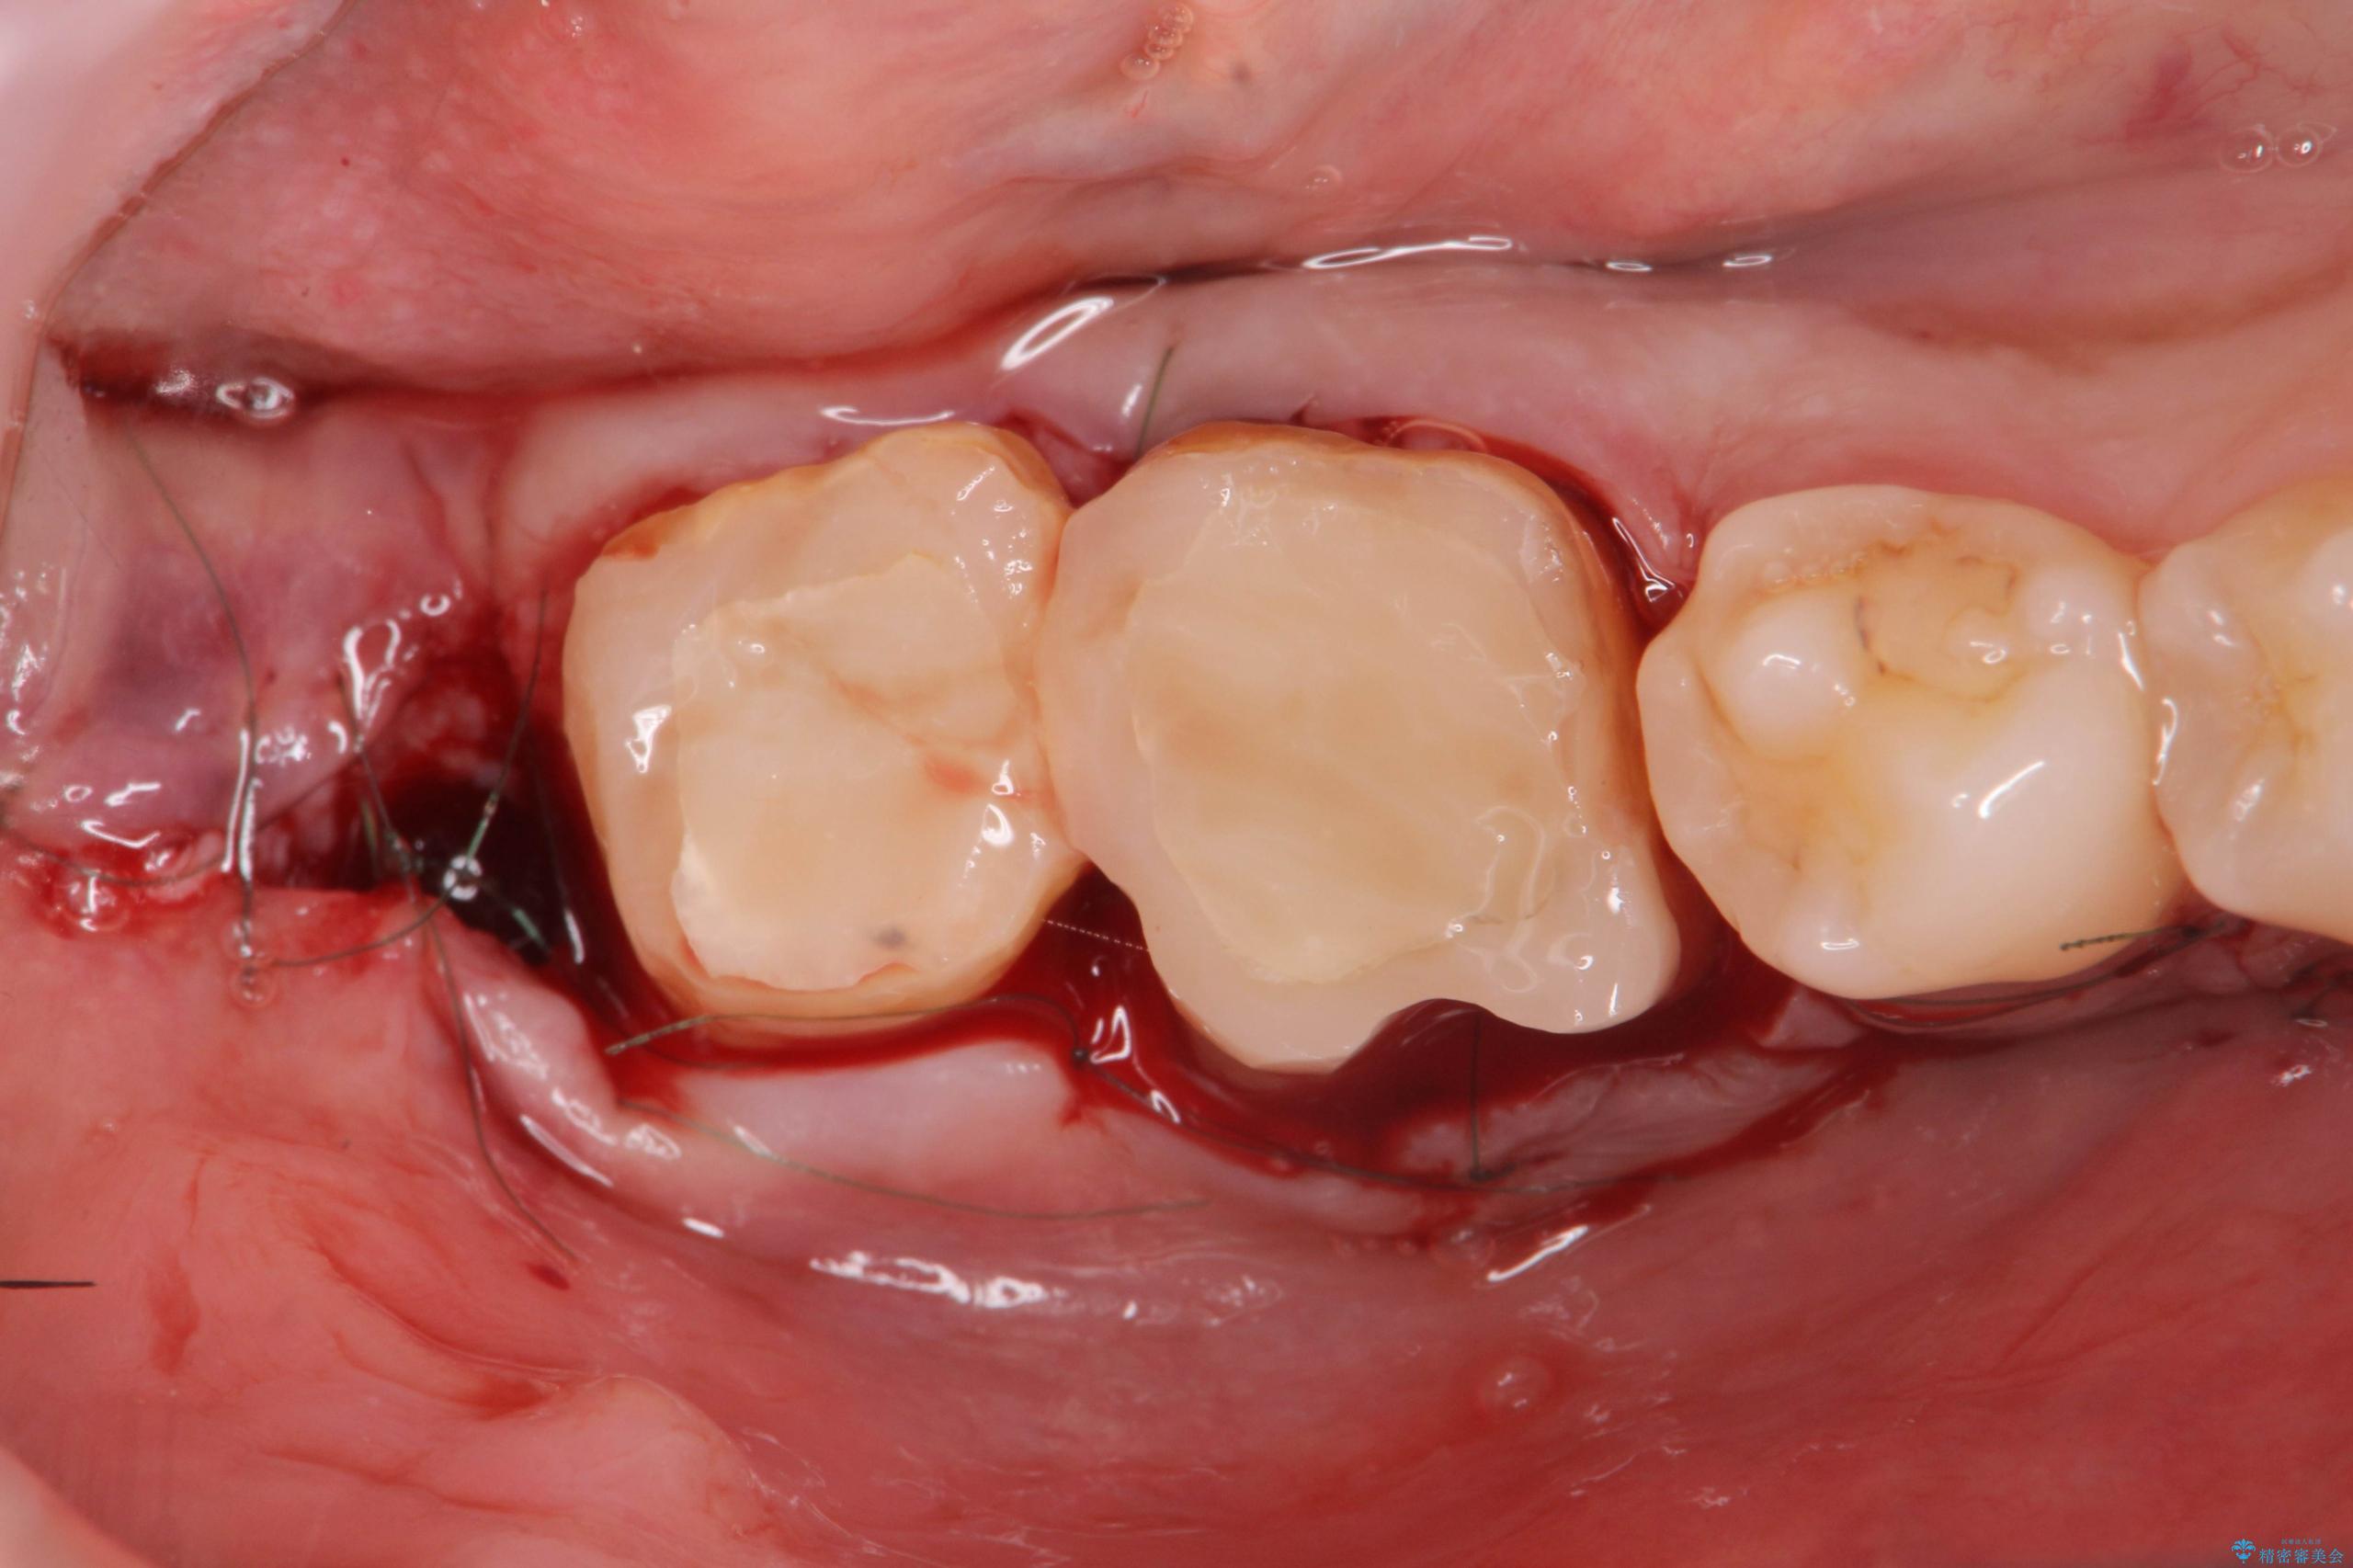

スペース狭小な銀歯を白くしたい 歯冠長延長術を併用したセラミック治療

金属のクラウンは薄く加工しても壊れないことがメリットですが、セラミッククラウンを装着するにはスペースが少なすぎ、このまま治療を進めると外れやすく壊れ易いセラミッククラウンの設計となるため、歯周外科を行い狭小なスペースの拡大を行うこととしました。

なんとかギリギリのスペースを確保するこおtができ、無事銀歯を外してセラミック治療を行うことができました。